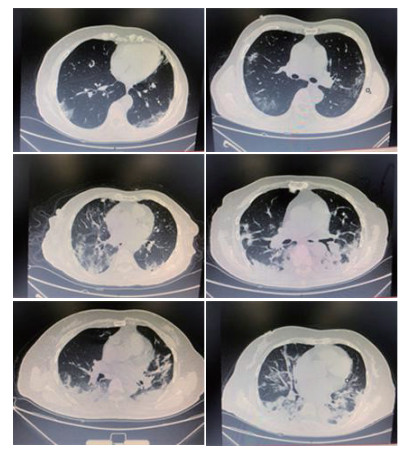

本研究所纳入的58例重型及危重型COVID-19患者,均于入院前1d或入院48h内完成CT影像学检查,其结果均符合典型COVID-19的影像学表现,主要特点为:所有患者均为双肺弥漫性病变,主要表现为双肺多发斑片影及磨玻璃影伴支气管充气征,以肺外带明显,多数患者存在双肺大面积实变影伴小叶间隔增厚,见图 1。

| 图 1 部分患者肺部CT影像学表现 Fig 1 Lung CT findings in typical patients |

已有的研究[7]显示:重症COVID-19患者的影像学异常比非重症患者更明显。重型和危重型COVID-19患者的肺部CT影像学典型改变是双侧多灶性斑片状磨玻璃影,随着病情的进展,可出现双肺多发性小叶和节段性实变[12],与本研究中患者的影像学表现基本符合。临床观察显示,多达30%的COVID-19患者会快速进展为ARDS[7],这一点解释了COVID-19的影像学表现常为广泛实变和磨玻璃样阴影(典型的急性肺损伤(ALI)影像学表现)[14]。本研究中部分患者的CT影像学表现较轻,但根据其呼吸窘迫程度,指氧饱和度,血气分析结果,其他器官功能情况,明确符合重型或危重型标准,分析其原因,考虑与患者年龄、自身体质、基础疾病和患病后情绪等因素有关。因此, CT影像学表现不能作为评估患者病情严重程度的唯一标准。